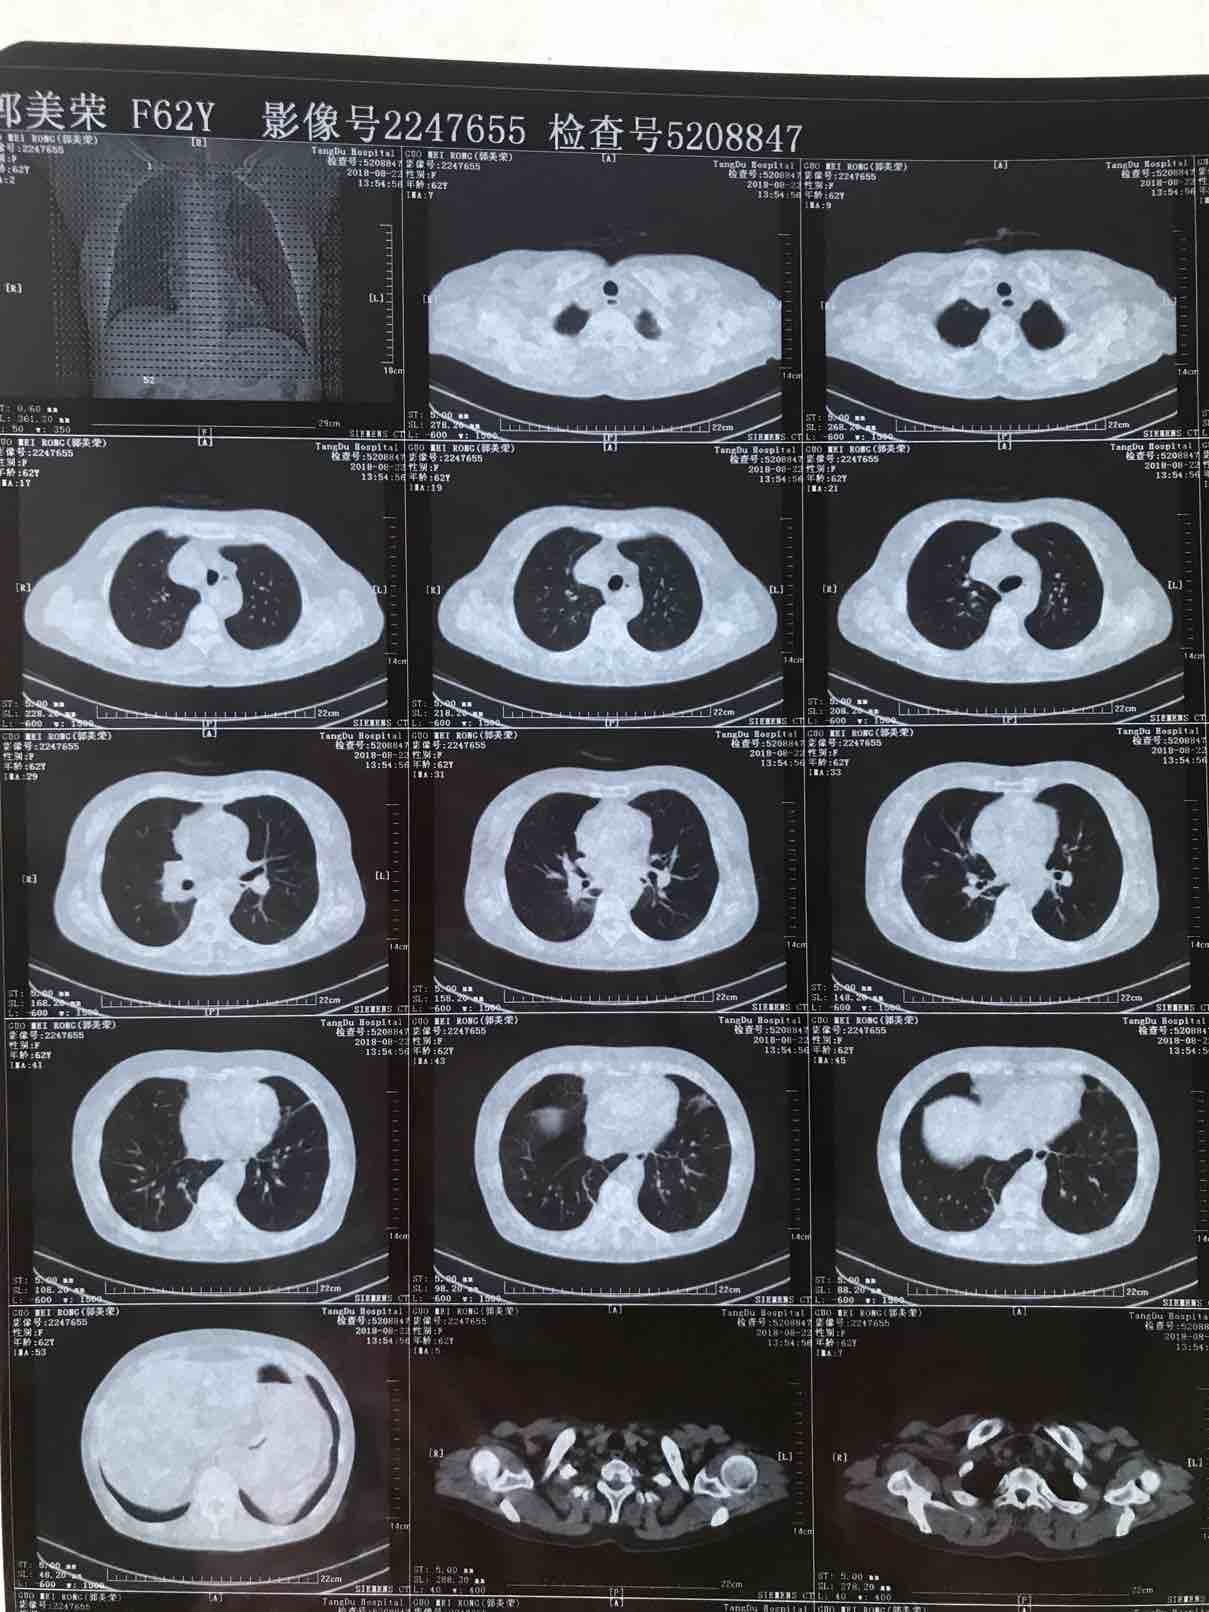

病历.患者,女,62岁,身高163,体重55公斤。2017年5月确诊肺腺癌晚期,胸膜转移,基因检测19突变,服用特罗凯至今。cea不敏感。近3个月体感变差,胸部牵扯痛,深呼吸痛,ca199从个位数升到74。周五复查发现进展了,如下图。

以下是8月的CT(1)

(2)